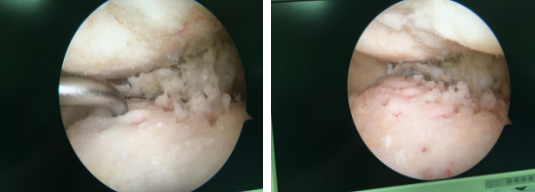

术中:病损的关节面清理

完善相关检查后,石院长徐主任手术团队为患者进行了关节镜下踝关节融合手术。手术医生在关节镜下用刨削器彻底清理关节的增生滑膜、骨赘、病灶、坏死物等,再清理掉关节内碎裂的软骨和软骨下硬化骨,露出胫骨远端、内外踝、距骨的松质骨,磨造粗糙面,确认解剖对位情况,使关节面能良好咬合;最后以三枚螺钉精准固定。